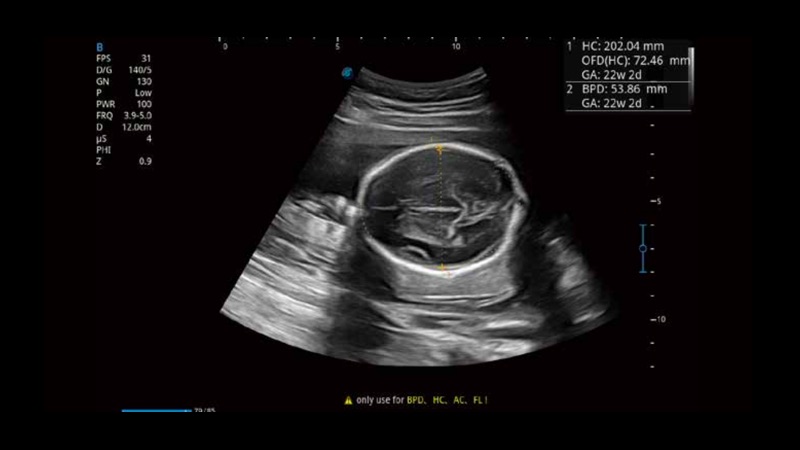

S-Fetus基于大數(shù)據(jù)深度學習算法,能夠幫助您在產(chǎn)前篩查過程中智能識別胎兒標準切面、自動測量并錄入報告。一個按鍵,即可智能、精準、高效地獲取胎兒生理指標,極大簡化您的產(chǎn)科檢查操作。

可快速對產(chǎn)科掃查切面完成胎兒生理學參數(shù)的自動測量,減少操作者按鍵次數(shù),大幅提升檢查效率。

自動識別頸項透明層并獲得NT值,為早孕胎兒畸形篩查提供有效測量工具,提高診斷效率和診斷信心。